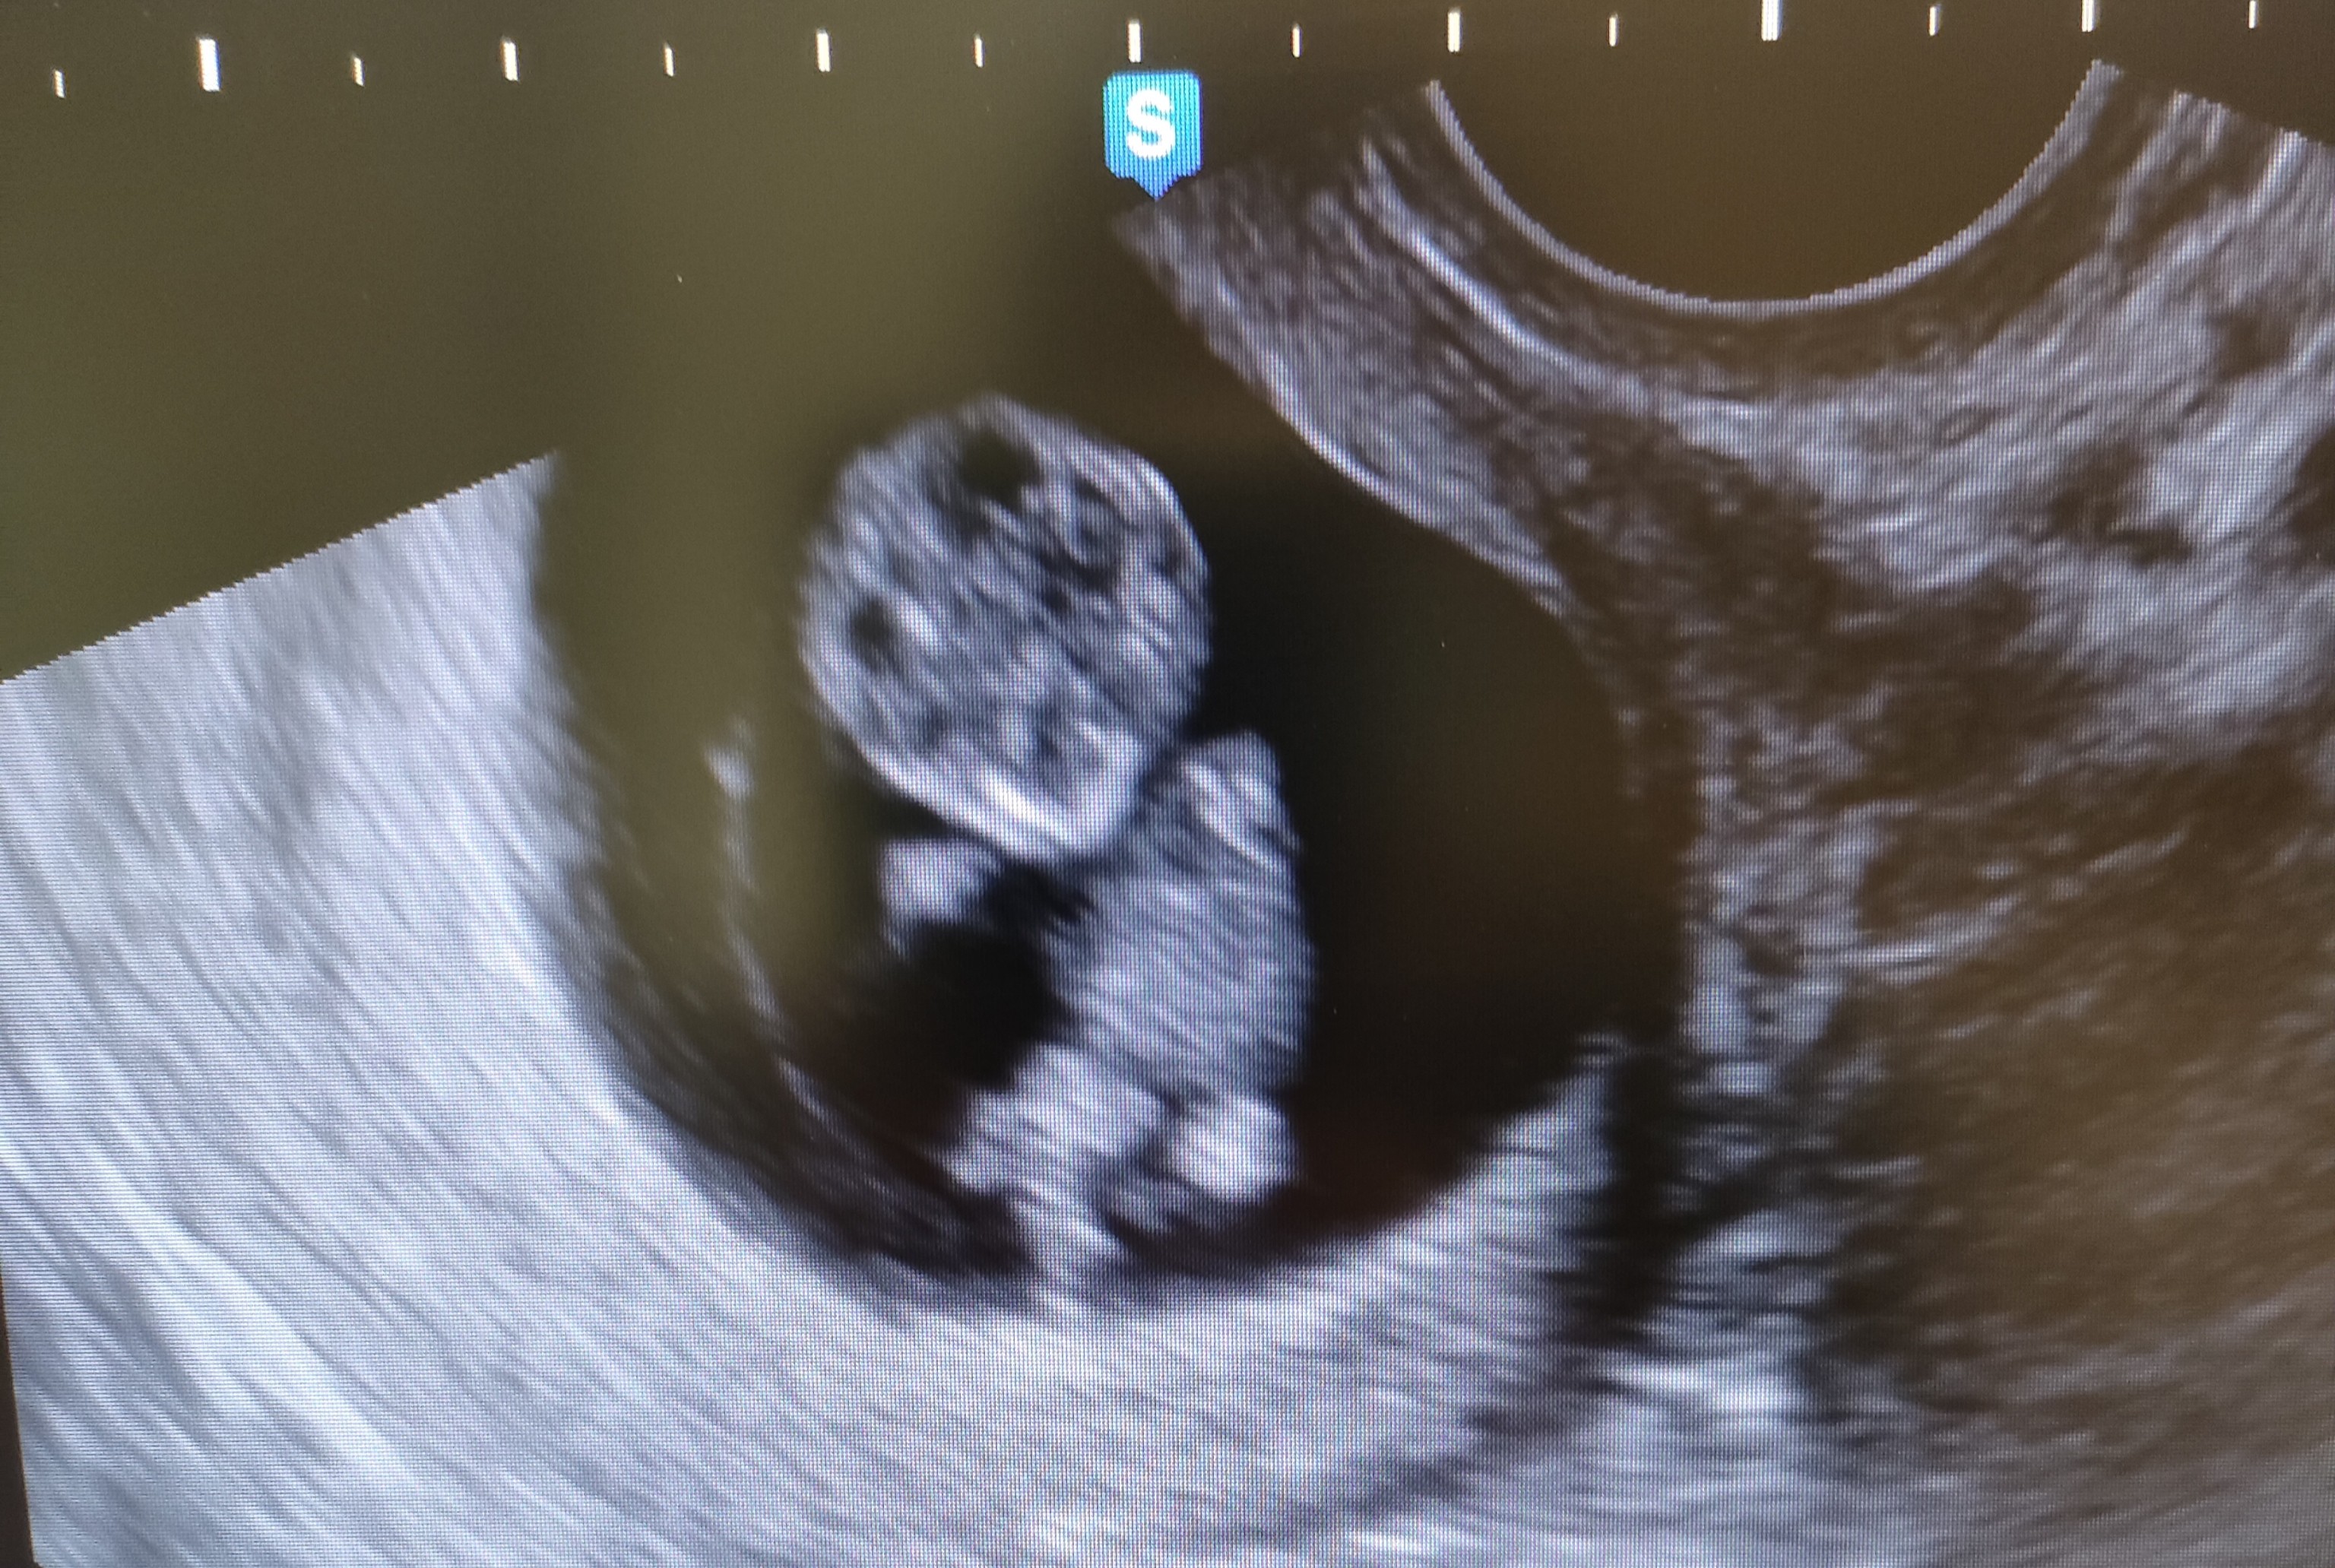

Ja po wizycie, babka straszna nawet zdjęcia nie dała tylko pozwoliła zrobić zdjęcie chociaż to 🙂 bobo ruszało się żywo i ma całe 3 cm 🙂❤️❤️❤️ termin teraz niby 5 listopada 🙂 ale trzymam się tego 4 listopada